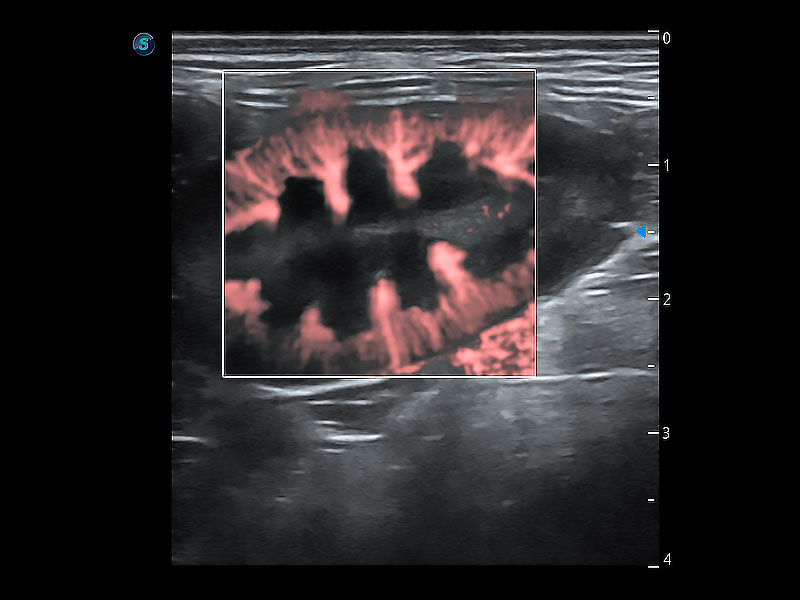

• Micro F 显微血流成像

极大提升超低速微细血流的检出能力,同时更精准地滤除软组织和超声信号,为兽用医生提供以往无法通过常规血流获得的疾病诊断信息。

• Bright Flow 立体血流成像

在传统二维血流成像的基础上,呈现血流的立体感,具有动感的生命力之美。即便是微小的血管也能轻松应对,提高了血流的视觉敏感性。